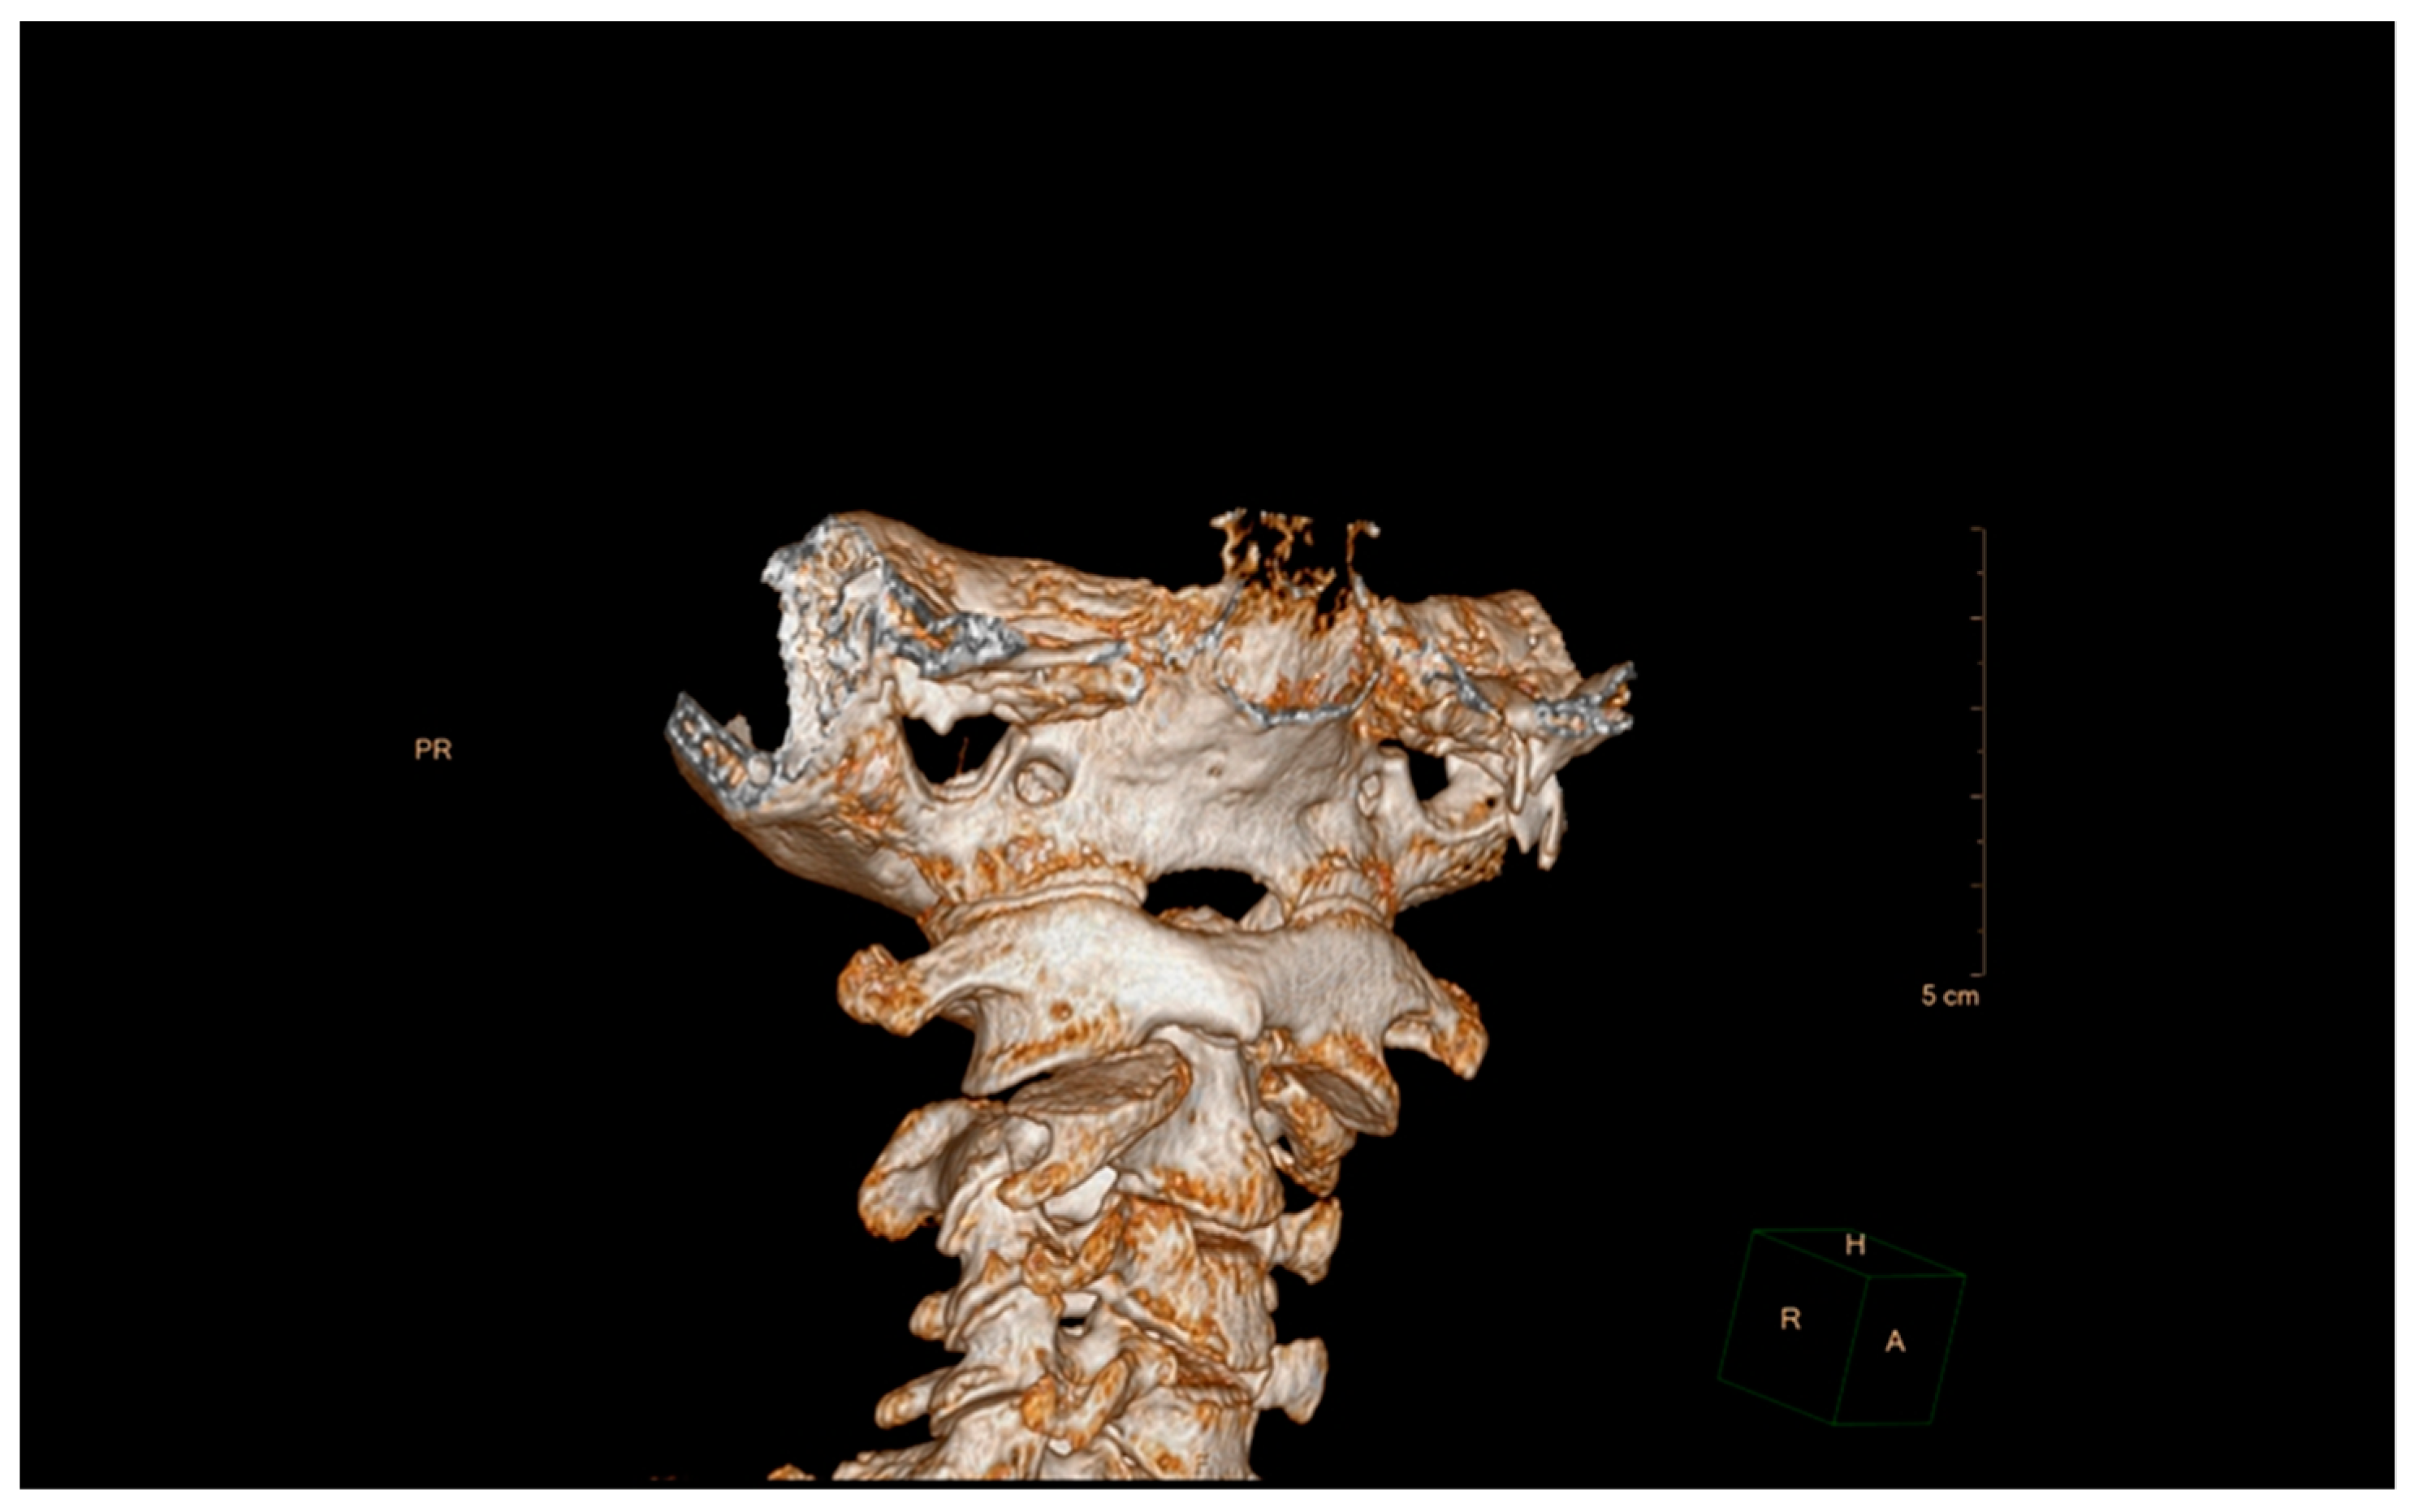

5.2. Computed Tomography (CT)